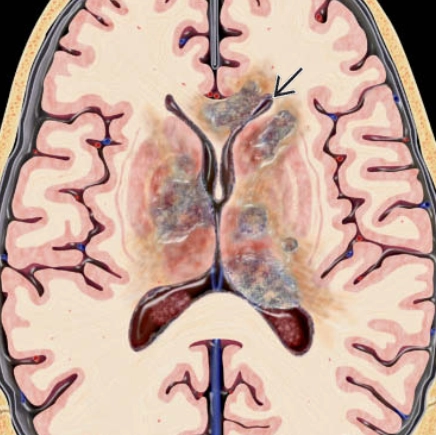

U lympho hệ thần kinh trung ương (Central Nervous System Lymphoma - CNS Lymphoma)

16/03/2026